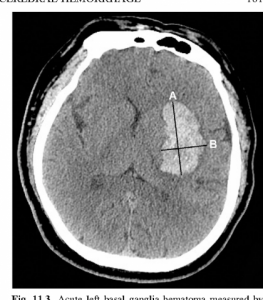

Fetiţa a fost dusă din Botoşani la Iași, zilele trecute, după ce a început să se simtă rău în timpul orelor de curs, acu­zând dureri de cap, senzaţie de vomă, intrând mai apoi într-o stare asemănătoa­re leşinului. La o unitate medicală din Botoşani s-a confirmat în urma investigaţiilor radiologice că este vorba despre un cheag de sânge şi a fost transferată la Iaşi pentru continuarea investigaţiilor. Aici medicii au descoperit că fetiţa are hipertensiune arterială, în ciuda vârstei mici, apoi i-au făcut analize pentru a vedea dacă este vorba despre malformaţii arterio-venoase, dar şi un RMN, însă nu s-a descoperit încă o eventuală cauză, scrie Ziarul de Iasi.

„Este un caz foarte ciudat, fiind un hematom care de obicei se întâlneşte la oameni vârstnici, de 80 de ani, pe fondul hiptertensiunii. Urmează de acum ca pediatrii să investigheze dacă este vorba despre stenoză de arteră renală. Momentan starea ei se ameliorează, însă a rămas deficitul motor din cauza cheagului“, au precizat medicii de la Spitalul de Neurochirurgie. Aceştia mai spun că în ultimii ani s-au prezentat mai multe cazuri de copii cu malformaţii ar­terio-venoase, existând şi cazul unui co­pil care la 14 ani a suferit un anevrism în timp ce juca fotbal.